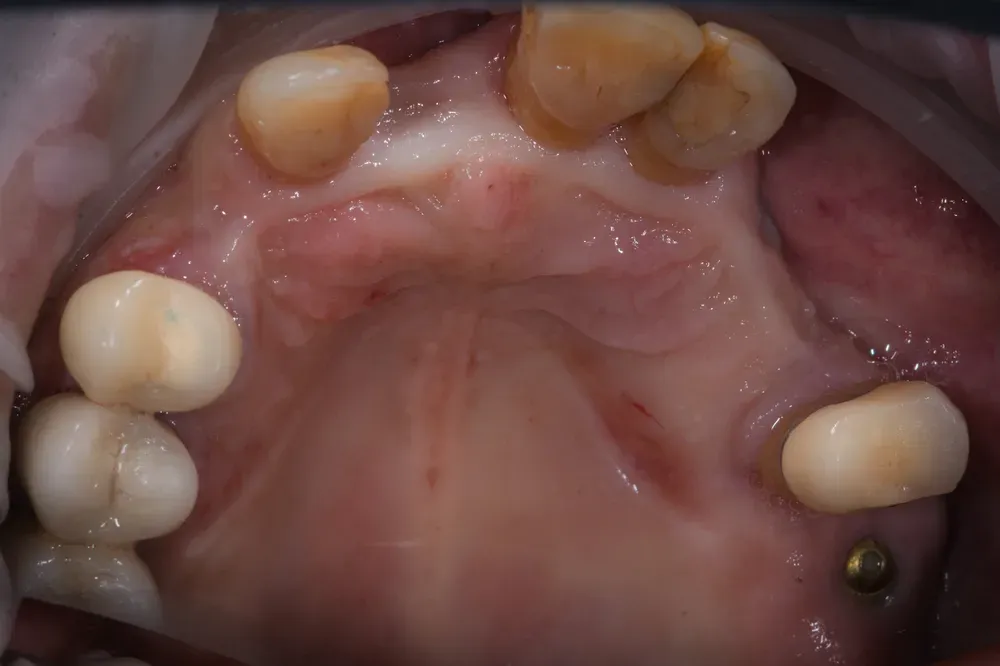

Nelle due figure sottostanti è evidente come la terapia, qui ancora in fase di estrazione dei denti non mantenibili, ottenga il ripristino totale (la rigenerazione) del tessuto alveolare e quindi una forma del tutto simile a quella naturale. E questo si ottiene solo con l’espansione mucosa del sito e senza xenoinnesti di connettivo. Inoltre, nei siti (alveoli) estrattivi non è stato inserito nulla per mantenere la forma: il mantenimento si ottiene solo con la forma del provvisorio che si inserisce per 4 mm all’interno con i “ponti ovoidi”.

Insomma la rigenerazione si ottiene con l’aria, anzi con il sangue che riempe i vuoti e poi grazie alle cellule che colonizzano i sito dai bordi e senza aggiunta di altri materiali. Bello no?

Come si ottiene la rigenerazione mucosa senza xenoinnesti di connettivo? Mediante la tecnica dei ponti ovoidi in un provvisorio inserito 4mm negli alveoli estrattivi, la mucosa si espande naturalmente. Il sangue riempie i vuoti iniziali e le cellule colonizzano il sito dai bordi senza aggiunta di materiali. È una rigenerazione biologica pura.